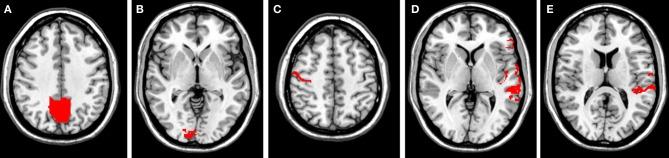

The spatial overlap across all four conditions was calculated for each seed region on a single subject and at the group level. Activation maps at the single-subject and group levels were highly stable, especially for the reading network (RNW). The lowest consistency measures were found for the visual network (VIN). At the single-subject level spatial overlap values ranged from 0.31 (VIN) to 0.45 (RNW).

计算了每个种子区域在单个受试者和组水平上的所有四个条件的空间重叠。激活图在单个受试者和组水平上非常稳定,尤其是在阅读网络(RNW)上。视觉网络(VIN)的一致性测量值最低。在单个受试者水平上,空间重叠值范围从 0.31(VIN)到 0.45(RNW)。